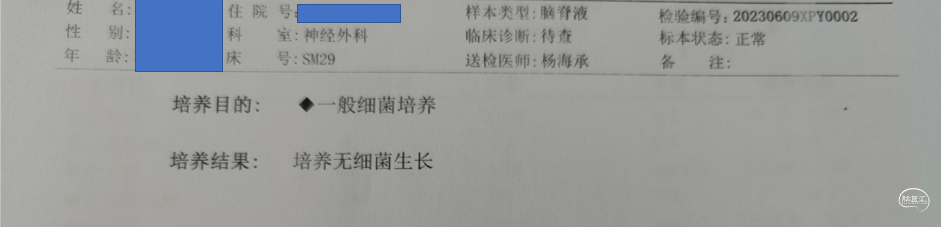

术后化验

2周后停抗生素